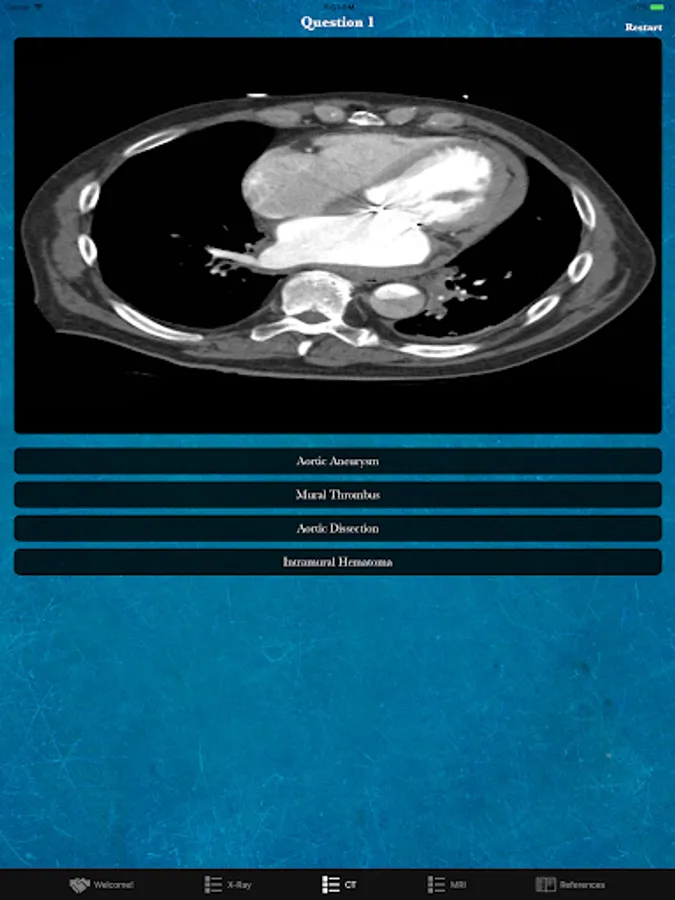

Rad Quiz is a free app developed as an introductory educational tool to expand your knowledge of medical imaging! Take our 20 question quizzes and evaluate your areas of strength and weakness. The quizzes test out three imaging modalities including X-ray, CT, and MRI. To learn more use our References tab to read up on the questions you missed. The content spans multiple specialities to give you a variety of content!